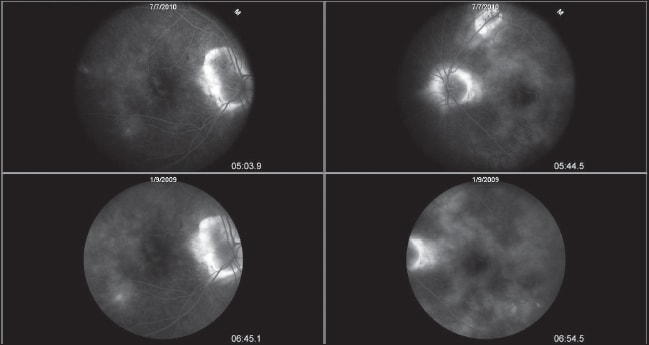

The patient underwent Retisert implantation in both eyes, which reduced the amount of leakage visible on angiography (Figures 1-4). Subsequently, she had cataract surgery with IOL implantation and IOP-lowering surgery in both eyes, to which she responded well.

Figures 1-4. Right and left eyes of a patient implanted with Retisert to control multifocal choroiditis with panuveitis. Note the reduced leakage on fluorescein angiography.

At the most recent follow-up visit, VA was 20/50 in the right eye and 20/20 in the left eye. Damage likely caused by inadequate control of inflammation by oral steroids may not allow further vision improvement in the right eye.